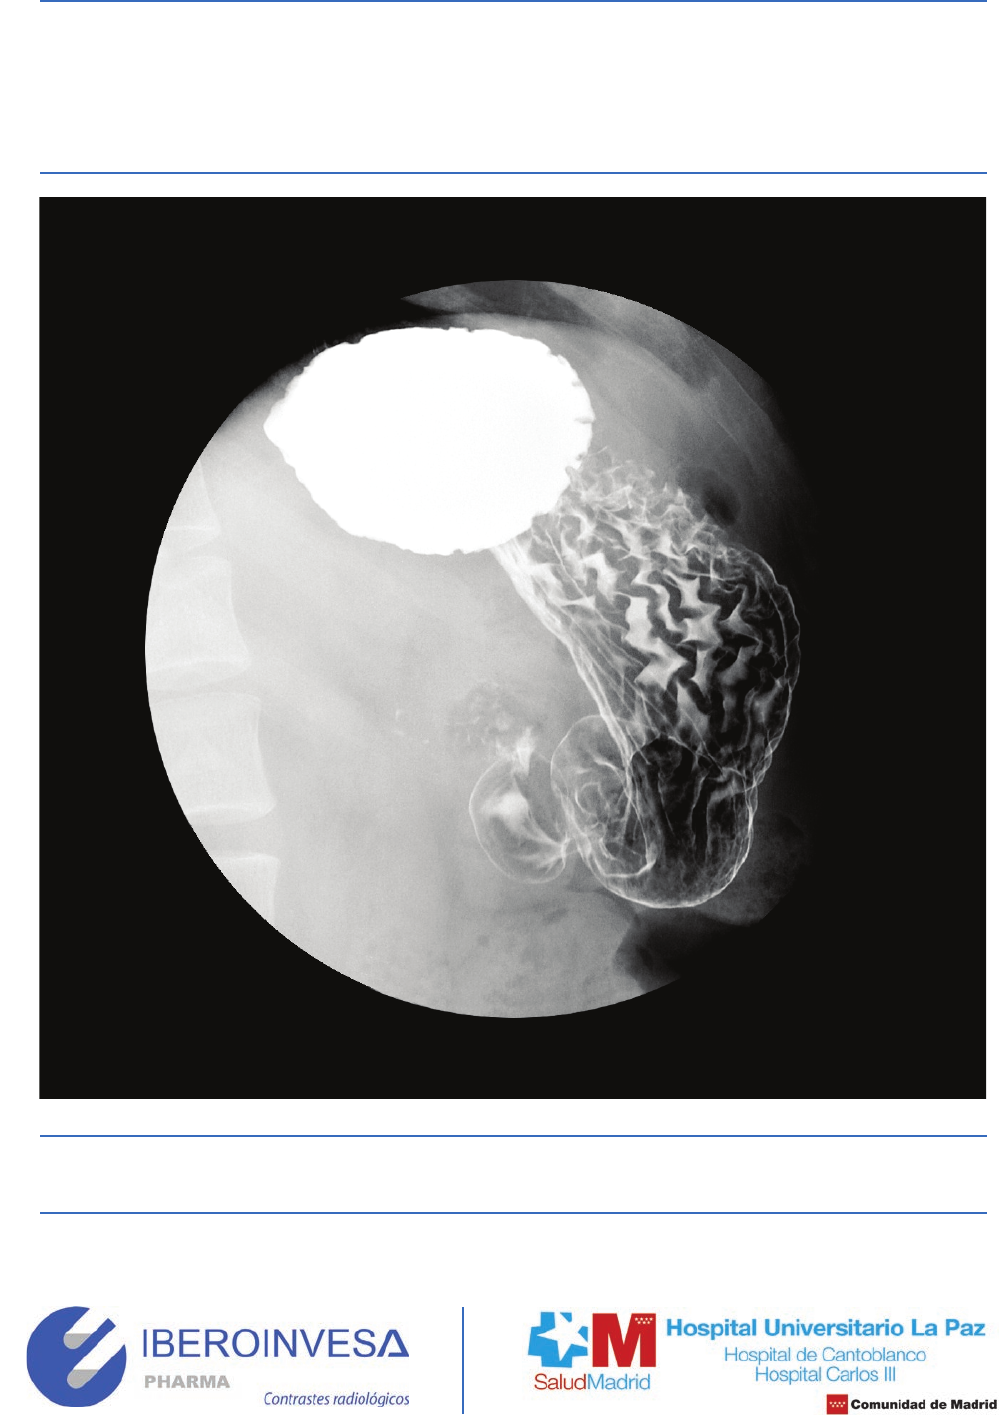

Pliegues gástricos normales con técnica de doble contraste.